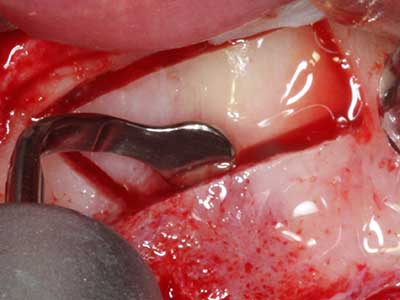

Пиезохирургията има допълнителни предимства при събиране на костни блокове. В допълнение към високата прецизност при остеотомията, описана по-горе, употребата на фините режещи накрайници значително намаляват загубата на материал. Голяма загуба на материал по време на събиране може да се очаква с дебелите накрайници, особено при употреба на борери Линдеман (Lakshmiganthan, Gokulanathan et al. 2012). Базалното разделяне, което е необходимо, особено за присадка на блок при ретромолар, е улеснено от специално създадени правоъгълни триони. В резултат на това, пиезохирургията е разглеждана като прецизна, улеснена и безопасна процедура за събиране на костни блокове в ретромоларното пространство (Happe 2007) (Фиг. 1-12).

Когато се извършват хирургични процедури върху кост в непосредствена близост до чувствителни структури като кръвоносни съдове или нерви, ротиращите инструменти създават значителен риск за ятрогенно нараняване. Пиезоелектрическите апарати могат да бъдат от помощ при препарация на костно покритие и отстраняване на твърда кост близо до нерви, особено за оголване на нервите след ятрогенно нараняване, както и по време на латерализация на нервите за резекционни и реконструктивни процедури или поставяне на имплант (Фиг. 17-20). Лекият контакт между пиезонакрайника и нерва по принцип не води до нараняване, но ако действате непредпазливо с трионообразни движения или приставки за остатъчен костен субстрат, може да причините временно или перманентно увреждане на нерва. Въпреки това, рискът от увреждане се счита за много по-малък, отколкото при употреба на триони или ротиращи инструменти (Pereira, Gealh et al. 2014).